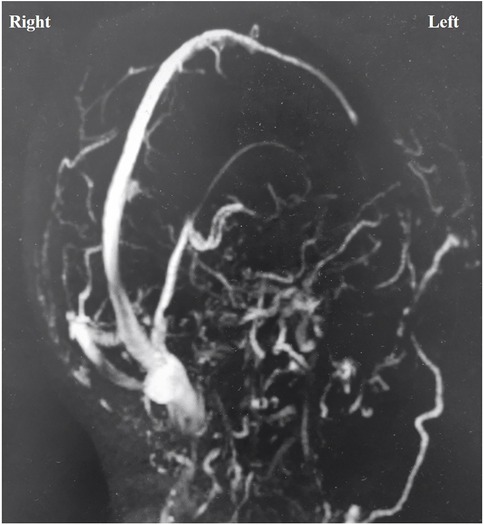

A retrospective review of 480 patients who underwent MVD for hemifacial spasm, trigeminal neuralgia, or glossopharyngeal neuralgia at our hospital from February 2008 to March 2019 identified one instance of acute brain swelling due to supratentorial subdural hematoma. This case involved a 60-year-old woman with a five-year history of trigeminal neuralgia and no hypertension, coagulopathy, or systemic diseases. During surgery, she was positioned laterally, and the arachnoid membrane was routinely opened. Cerebrospinal fluid (CSF) drained slowly, causing slight cerebellar collapse. Ten minutes after dura entry, the cerebellopontine cistern was opened, leading to a sudden CSF gush and almost immediate acute brain swelling, filling the surgical field within 10 s (Supplementary Video S1). Throughout, the patient's head position remained unchanged, blood pressure and heart rate were stable, anesthesia was maintained, and the procedure followed standard protocols without any unusual circumstances. The cause of the brain swelling was unclear, given normal manipulation, unobstructed airway, and absence of surgical bleeding. We had to manage the brain swelling while considering the possibility of remote hemorrhage. Mannitol (250 ml ivgtt) and dexamethasone (10 mg i.v.) were administered to lower intracranial pressure (ICP), while cerebrospinal fluid was gradually drained from the compact subdural space. The surgical field was restored within 40 min, and ICP gradually decreased. Despite the surgical field being narrower than initially, and elevated ICP detected under the suction device, we proceeded with supracerebellar artery decompression of the trigeminal nerve in a confined space (Supplementary Video S2). Bilateral pupil monitoring during surgery showed normal results. A postoperative CT scan immediately revealed contralateral acute supratentorial subdural hematoma (SDH) with a midline shift of approximately 4 mm (Figure 1). The patient awoke from anesthesia with a Glasgow score of 15, and no obvious signs of neurological dysfunction were observed. Moreover, within 8 h after the operation, three head CT scans were completed, confirming that the volume of the subdural hematoma remained stable and did not increase further. At the same time, the patient's clinical symptoms were stable, with no obvious symptoms of increased intracranial pressure such as headache or projectile vomiting. Therefore, we did not place an ICP probe for continuous monitoring of intracranial pressure, but continued to observe the clinical symptoms and signs. Fortunately, when the CT was rechecked 21 h after the operation, it was found that most of the subdural hematoma had dissipated (Figures 2A,B). The patient was discharged eight days later without neurological impairments.

Figure 1

Four-panel image of CT brain scans labeled A, B, C, and D. Panel A shows a transverse section with sinus involvement. Panel B shows a cross-section with brain matter visible. Panel C displays another transverse section highlighting cranial structures. Panel D shows a cross-section focusing on the brain's central area.

Figure 1. Postoperative CT scan. A,B: CT at 0 h post-operation showed that there was no hemorrhage in the operation area of left cerebellopontine angle, but there was right supratentorial subdural hematoma (1 cm thickness). C,D: CT at 4 h post-operation showed that hematoma was stable.